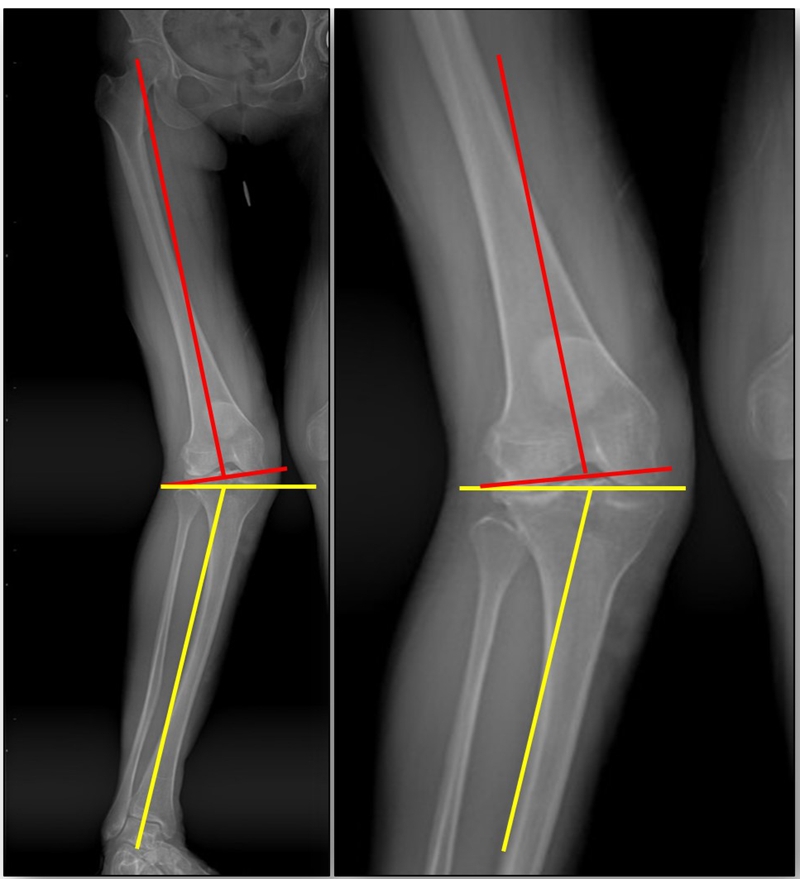

以两例病例展示术前设计的五步。患者一,女性,42岁,左膝疼痛2年,加重1年。

步骤一:判断内外翻畸形

画下肢机械轴,股骨头中心链接踝关节中心判断患者为内翻畸形还是外翻畸形。此患者为外翻畸形。

步骤二:判断畸形部位

量股骨远端外侧角和胫骨近端内侧角,判断畸形在股骨、胫骨还是关节内。此患者股骨侧有畸形,LDFA=76°,MPTA=81°,无关节内畸形。

步骤三:设定目标力线

以关节线为基准参考线,设定目标力线与关节线垂直。

步骤四:确定合页位置和截骨线方向

此患者计划股骨内侧闭合楔,胫骨内侧开放楔。

步骤五:Miniaci法测量角度

以股骨侧合页为旋转中心,以股骨头中心到合页的距离为半径,进行旋转,直到该线段与目标力线相重合,此时重合角度即为股骨需要闭合的角度,同时胫骨侧也能计算出开放的角度。此患者需要股骨闭合14°,胫骨开放8°。